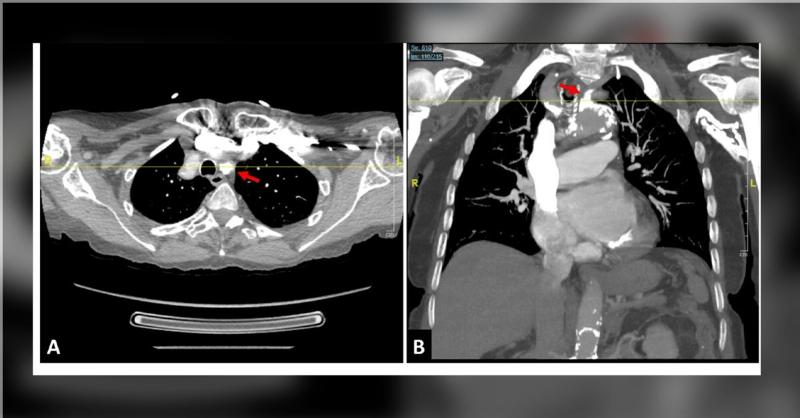

An 89-year-old woman, known for hyperlipidemia and untreated hypertension, presented after tests revealed a severe blockage in her left subclavian artery with aortic arch and descending aorta calcifications. She had experienced progressive vertigo, unsteady gait, falls, blurry vision, and left arm numbness/tingling for weeks. Physical examination n